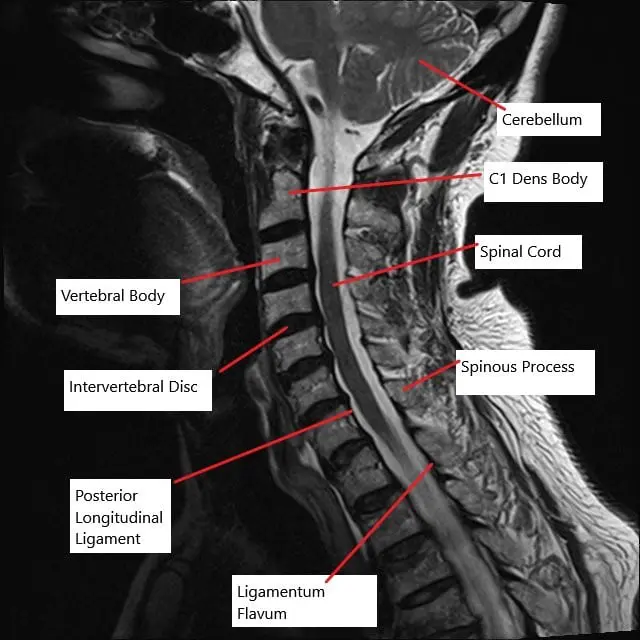

MRI of the cervical spine in the sagittal section showing multiple bulging intervertebral discs.

The cervical spine consists of seven vertebrae that are separated by intervertebral discs. These discs act as shock absorbers, allowing for movement while also protecting the spinal cord, which runs through the spinal canal formed by the vertebrae. The spinal cord gives off nerves at each vertebral level, which control various body functions. When the vertebrae or discs degenerate, the spinal canal can narrow, compressing the spinal cord or nerves and leading to various neurological symptoms.